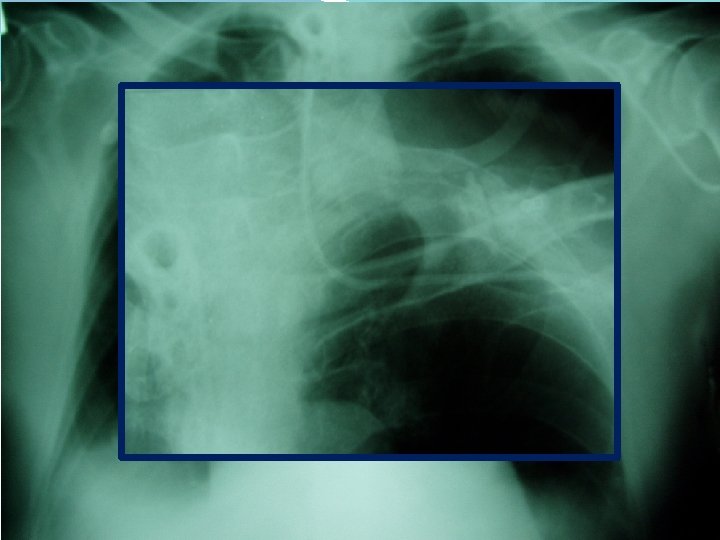

Central venous catheter - What to do after cannulation sterile cover control chest X-ray exclude PNO check position of catheter

Central venous catheter - Complications arythmias PNO bleeding punction of arteria damage of plexus brachialis air emboly thrombosis (v. femoralis) infection, sepsis